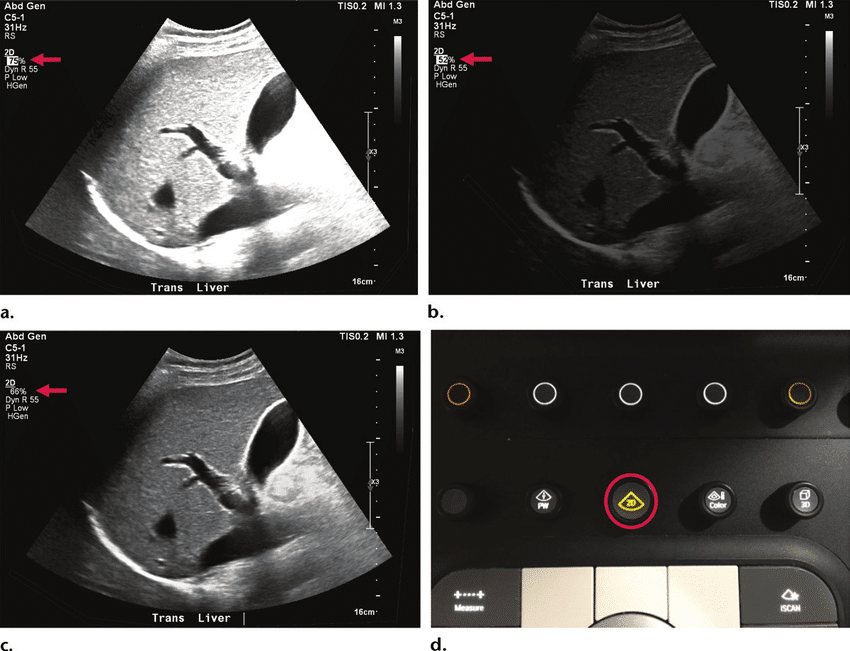

¿Quieres ver cómo funciona? Este vídeo te muestra exactamente cómo el ajuste de Profundidad y Ganancia transforma la imagen en tiempo real.